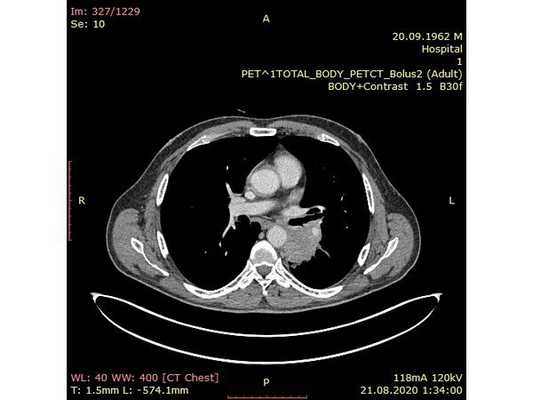

Чтобы провести первичное стадирование опухоли, пациенту проведена позитронно-эмиссионная томография в сочетании с компьютерной томографией (ПЭТ-КТ). По данным исследования, выявлена метаболически активная опухоль в корне левого лёгкого с бугристыми контурами размерами 41 х 43 мм. В толще опухоли проходят нижнедолевой бронх и бронх 6-го сегмента левого лёгкого, просветы бронхов значительно сужены. Нижняя доля левого лёгкого уменьшена в размерах за счёт того, что сегменты 6, 9 и 10 субтотально (частично) инфильтрированы и безвоздушны. Лимфатические узлы корня лёгкого и средостения не увеличены в размерах и не накапливают радиофармпрепарат (РФП), который был введён пациенту перед обследованием внутривенно. Других очаговых образований и очагов гиперметаболизма в организме не обнаружено.

При этом отмечено, что опухоль распространяется в средостение по нижней стенке левого главного бронха и широко прилежит к нижнегрудному отделу аорты (по заключению специалиста ПЭТ-КТ — имеется инвазия опухоли в ткани средостения и возможное врастание в стенку аорты). При самостоятельном пересмотре изображений отмечено, что "опухолевая" ткань, которая распространяется по нижней стенке левого главного бронха в средостение, не накапливает РФП (т. е. не является злокачественной), а стенка аорты в области "инвазии" опухоли имеет ровный чёткий контур и адвентициальную границу, что также свидетельствует об отсутствии онкологического процесса в этой области.